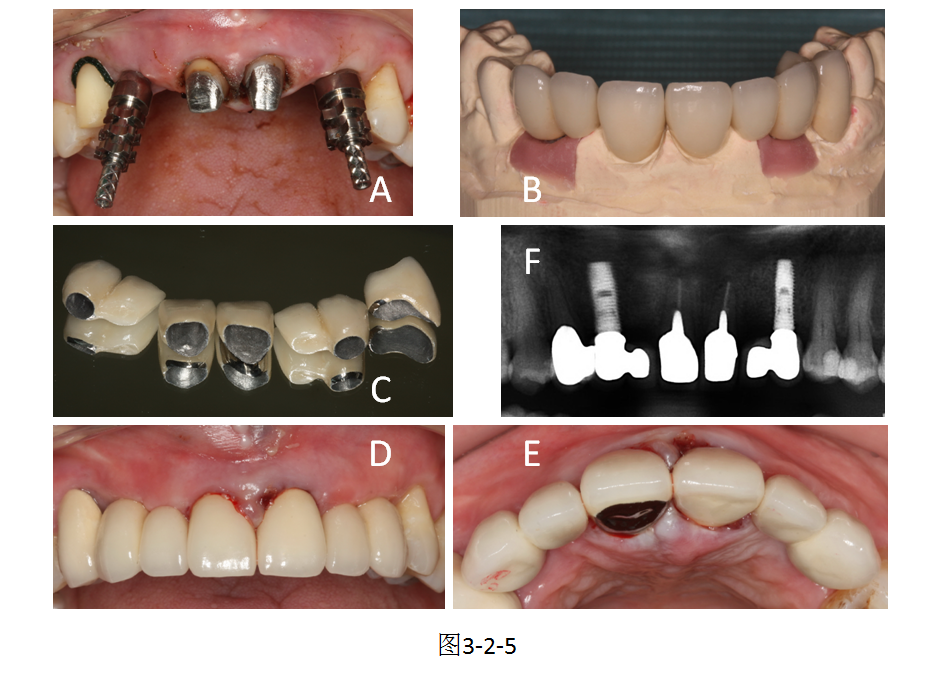

针对前牙区牙体缺损、牙列缺失患者,采用即刻种植技术植入种植体,联合个性化固定桥修复,恢复牙列完整性与美观度,效果稳定。

展示口腔种植基台植入术后口内状态,体现种植修复精准稳固的临床效果。

右上双尖牙长期龋损拔除,第一磨牙前倾直接影响A5位点的种植。根据试排牙最终修复效果的需要,手术之前先调磨A6近中邻面,减小近中倒凹,后期单冠修复,确保了A5植入的正常角度。...